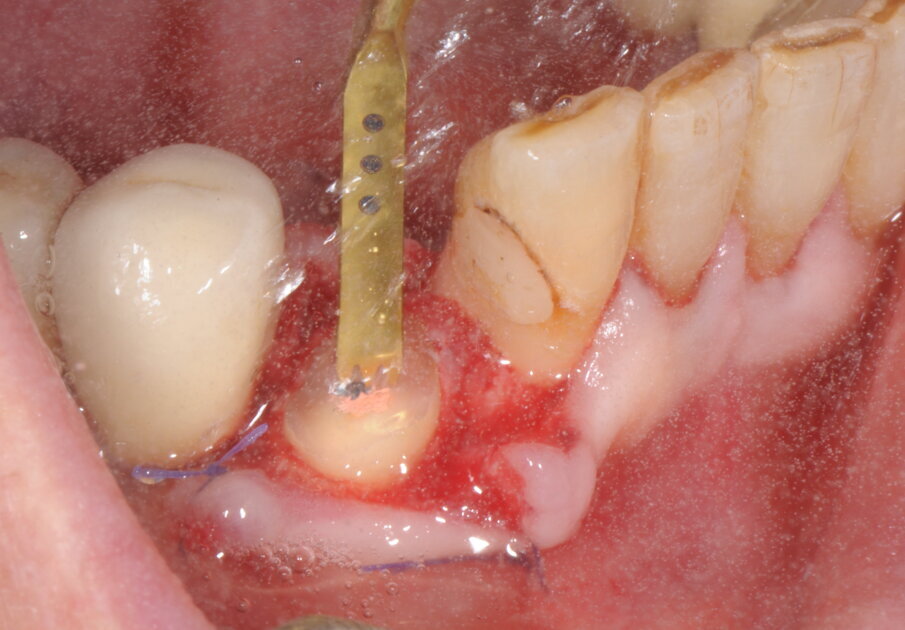

Il caso clinico che andremo a descrivere vede interessata una paziente di anni 69, di sesso femminile, in buona salute, non fumatrice, con frattura del 4.3 ricostruito in precedenza con una ricostruzione diretta in resina composita dopo trattamento endodontico. In accordo con la paziente abbiamo elaborato un piano di trattamento che prevedeva l’estrazione della porzione radicolare residua del canino inferiore di destra, l’inserimento simultaneo di un impianto osteointegrato e un carico protesico immediato. In anestesia locale è stata praticata un’incisione intrasulculare, con minimo scollamento dei tessuti molli, per accedere alla superficie di frattura (Fig. 1). La procedura chirurgica, valutato lo spessore ridotto della corticale vestibolare in accordo con i protocolli PIEZOSURGERY applicati alle estrazioni, ha previsto la regolarizzazione della linea di frattura apicalmente alla giunzione amelo-cementizia, mediante un inserto OT7 e, successivamente, un frazionamento radicolare in direzione mesio-distale con inserto OT7S-3 (Figg. 2, 3).

Fig. 1

Fig. 2

Fig. 3